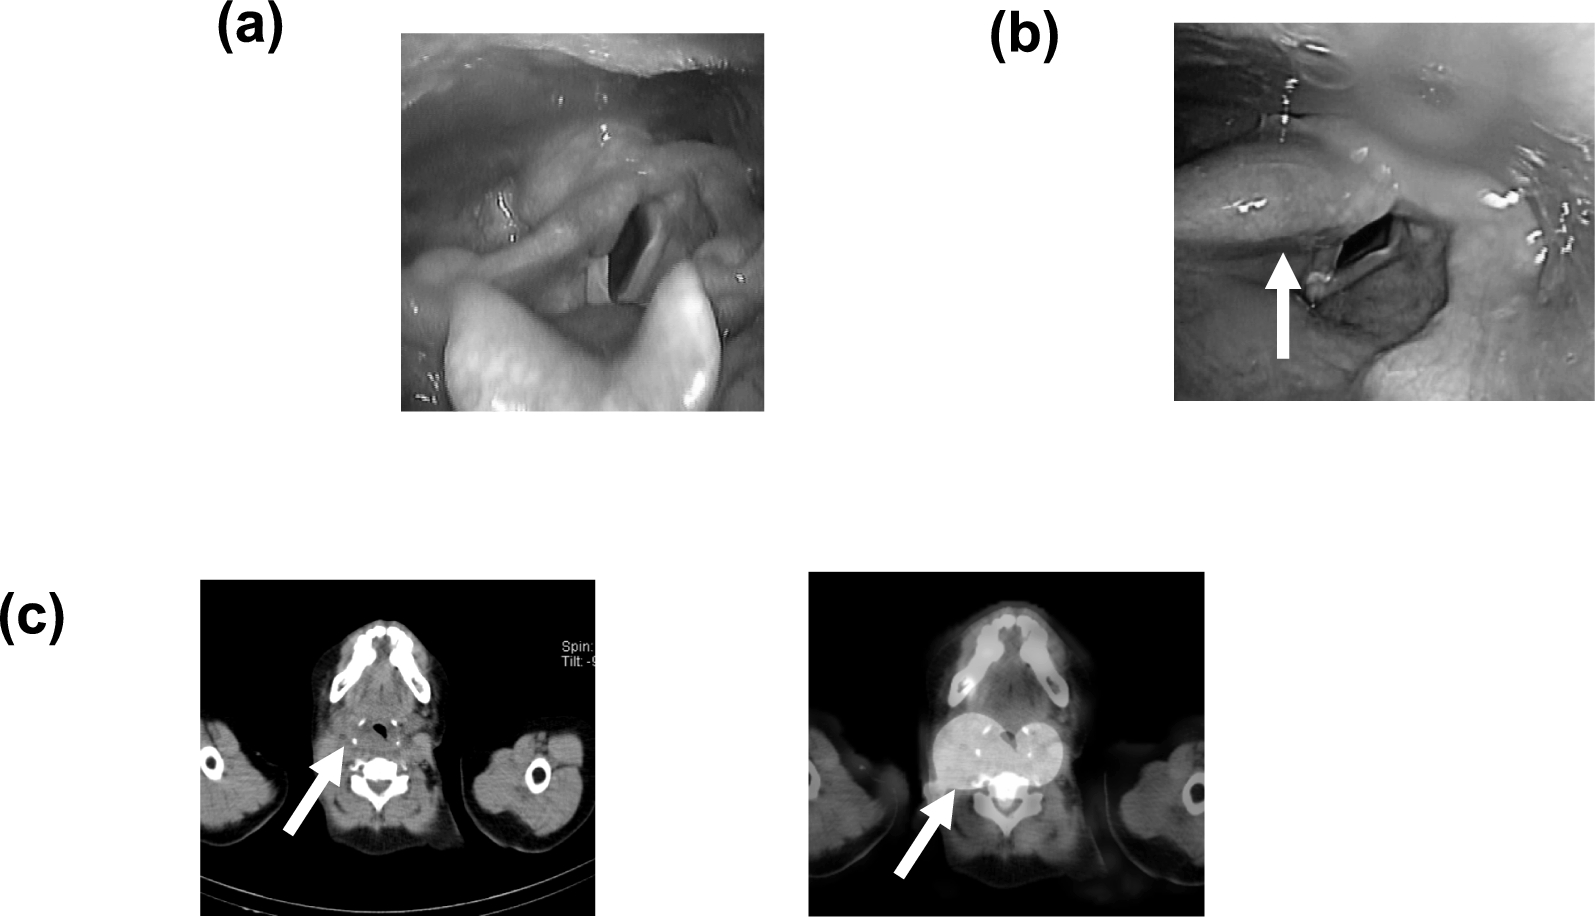

Quantitative evaluation of thyroid bed accumulation in I-131 radiotherapy: a comparison of laryngeal edema and non-edematous cases

At our institution, approximately 70 patients are treated with I-131 therapy at a standard dose of 3.70 GBq each year, and...